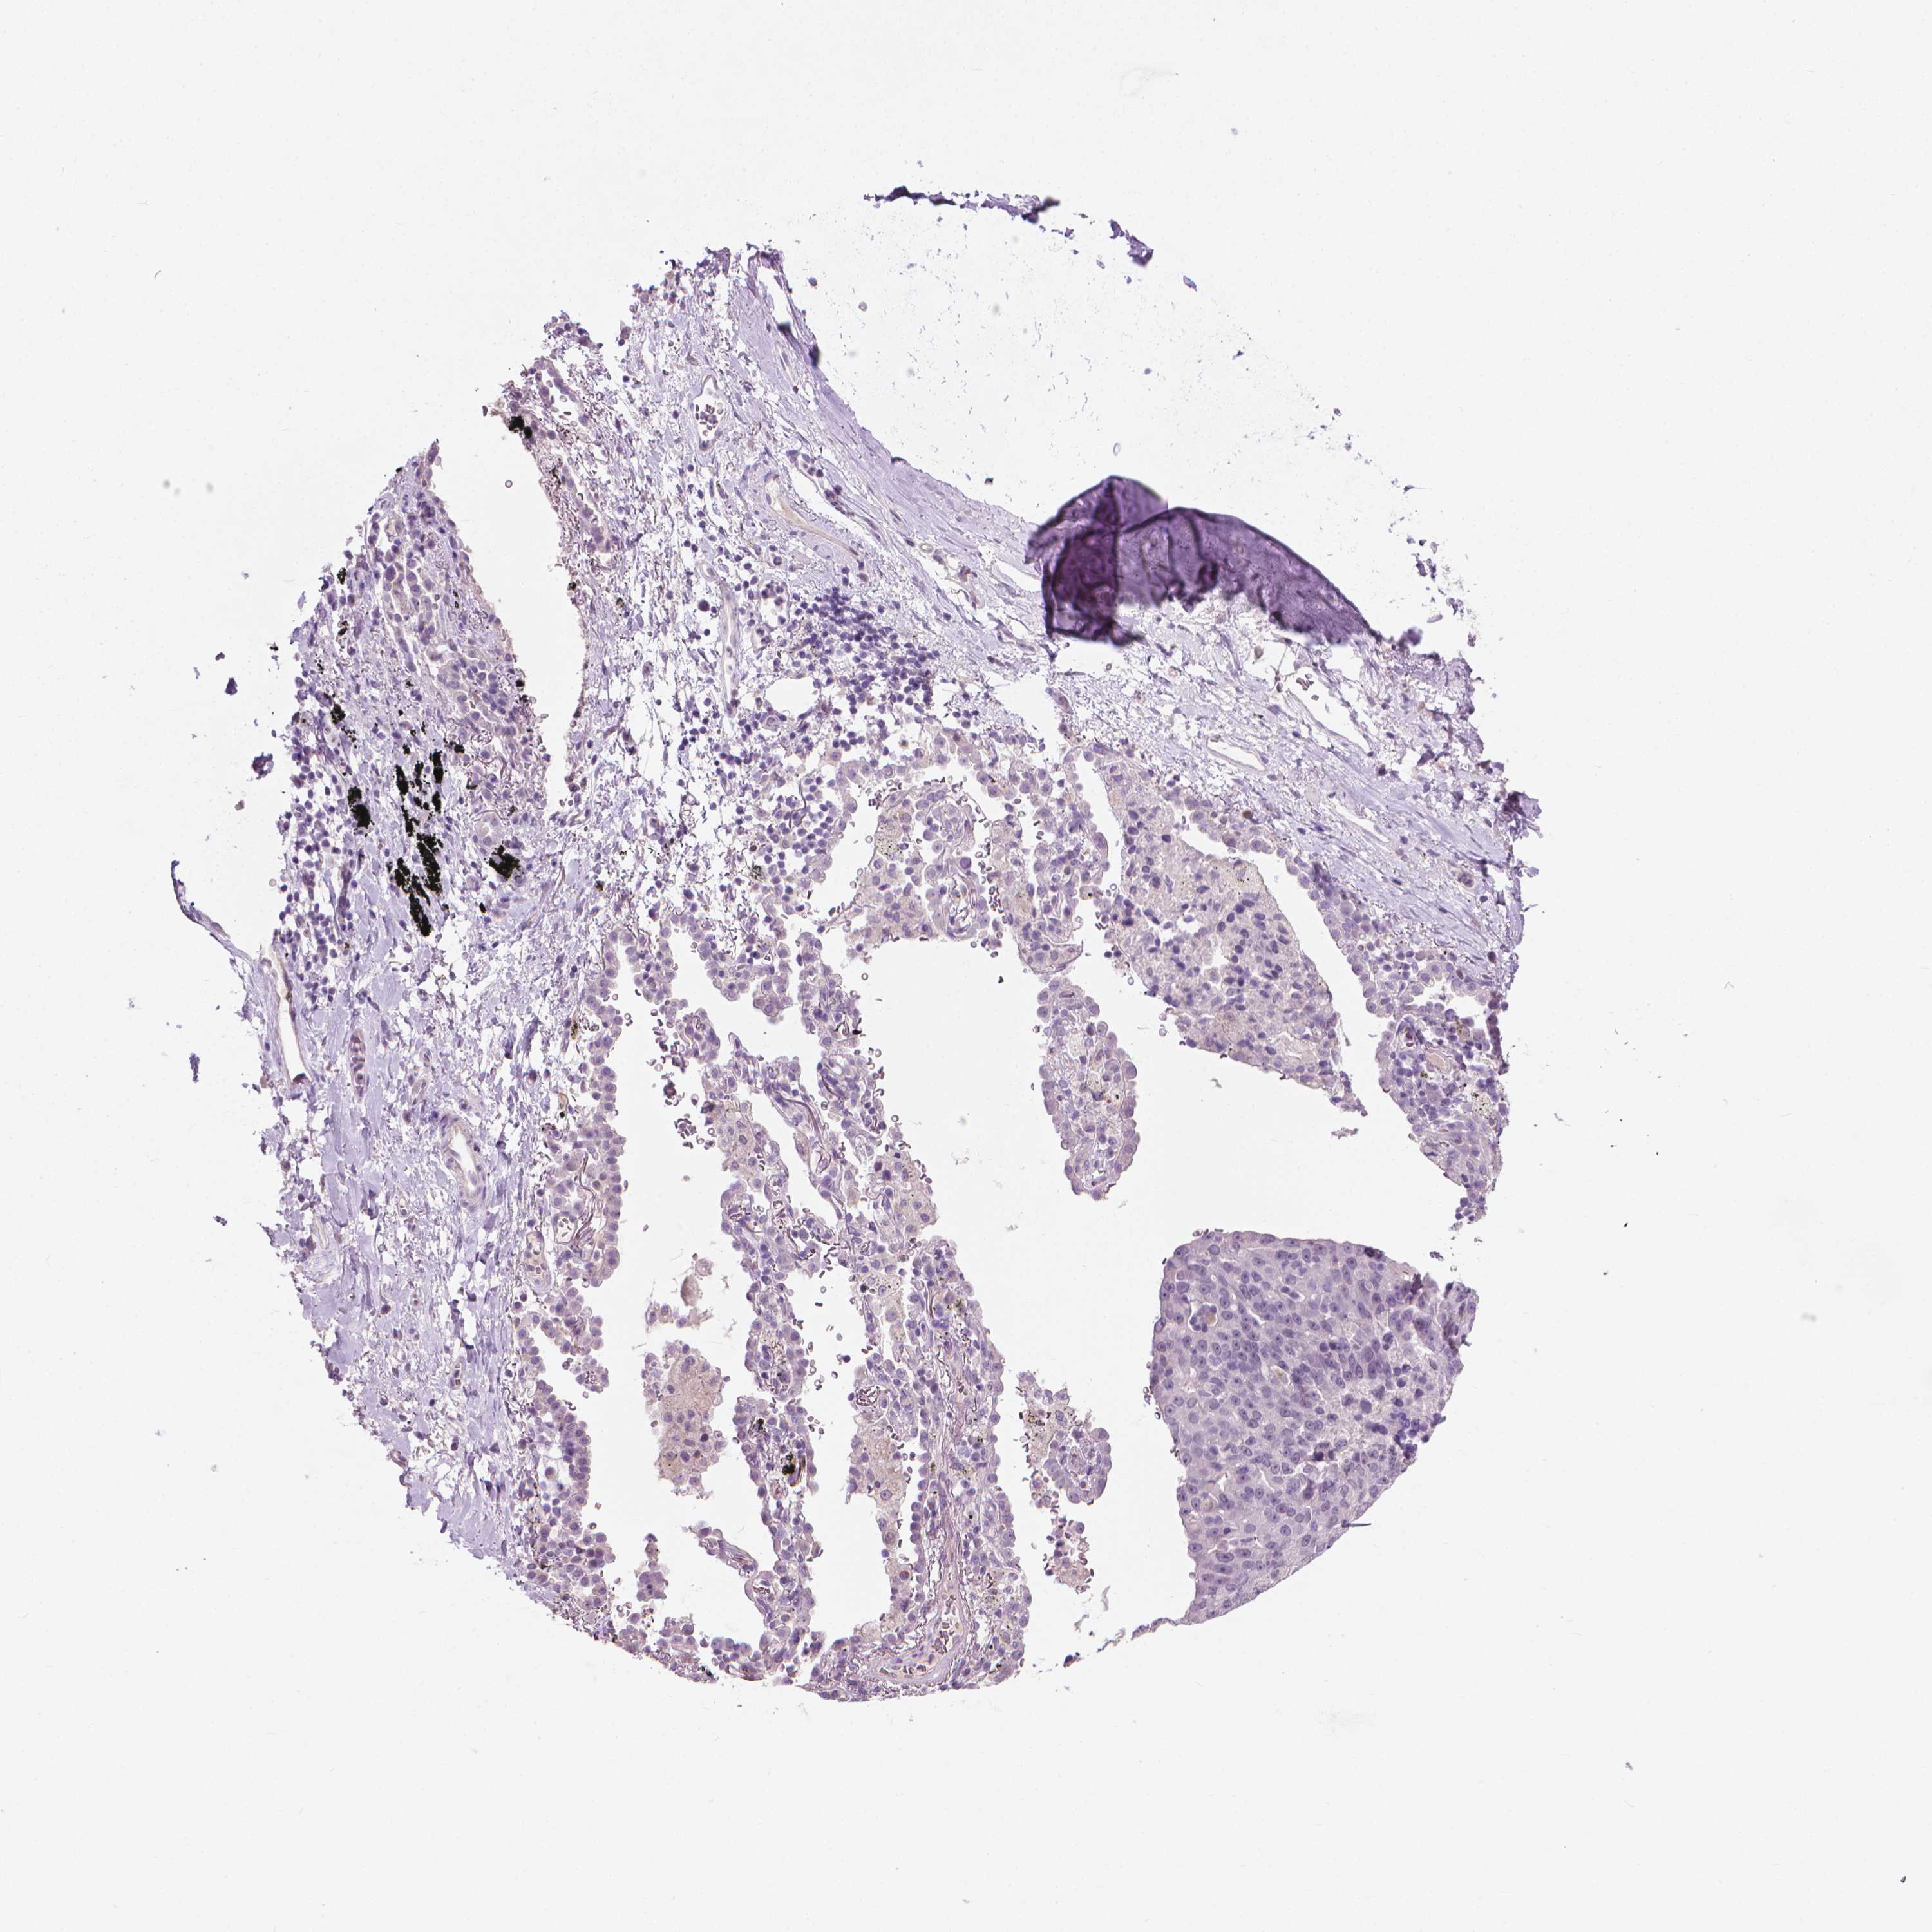

LUNG SQUAMOUS CELL CARCINOMA (TCGA) - Interactive survival scatter ploti

The Survival Scatter plot shows the clinical status (i.e. dead or alive) for all individuals in the patient cohort, based on the same data that underlies the corresponding Kaplan-Meier plots. Patients that are alive at last time for follow-up are shown in blue and patients who have died during the study are shown in red.

The x-axis shows the expression levels (FPKM) of the investigated gene in the tumor tissue at the time of diagnosis. The y-axis shows the follow-up time after diagnosis (years). Both axes are complimented with kernel density curves demonstrating the data density over the axes. The top density plot shows the expression levels (FPKM) distribution among dead (red) and alive patients (blue). The right density plot shows the data density of the survived years of dead patients with high and low expression levels respectively, stratified using the cutoff indicated by the vertical dashed line through the Survival Scatter plot. This cutoff is automatically defined based on the FPKM cutoff that minimizes the p-score. The cutoff can be changed by dragging the vertical line or by entering a cutoff value in the square labeled "Current cut-off".

Under the Survival Scatter plot the p-score landscape (black curve; left axis) is shown together with dead median separation (red curve; right axis). Dead median separation is the difference in median mRNA expression between patients who have died with high and low expression, respectively. It is calculated as follows: median FPKM expression of dead patients with high expression - median FPKM expression of dead patients with low expression. This is intended to aid the user in visually exploring custom cutoffs and the associated p-scores and dead median separation.

Individual patient data is displayed and can be filtered by clicking on one or more of the category buttons on the top of the page. Categories describing expression level and patient information include: high, low, alive, dead, female, male and tumor stages. The scale of the x-axis can be toggled between linear and log-scale by clicking on the "x log" button. Mouse-over function shows TCGA ID, patient information and mRNA expression (FPKM) for each patient.

& Survival analysisi

Kaplan-Meier plots summarize results from analysis of correlation between mRNA expression level and patient survival. Patients were divided based on level of expression into one of the two groups "low" (under cut off) or "high" (over cut off). X-axis shows time for survival (years) and y-axis shows the probability of survival, where 1.0 corresponds to 100 percent.

KRT73 is not prognostic in Lung Squamous Cell Carcinoma (TCGA)

TCGA RNA samplesi

RNA-seq data is reported as average FPKM (number Fragments Per Kilobase of exon per Million reads), generated by the The Cancer Genome Atlas (TCGA) .

Normal distribution across the dataset is visualized with box plots, shown as median and 25th and 75th percentiles. Points are displayed as outliers if they are above or below 1.5 times the interquartile range. FPKM values of the individual samples are presented next to the box plot.

Average pTPM 0.0

Number of samples 489